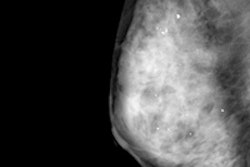

A 62-year-old woman with nonpalpable 9-mm invasive ductal carcinoma only seen on ultrasound (below). A radial sonogram obtained at the 5 o'clock position in the left breast shows a hypoechoic irregular mass. All mages courtesy of Dr. Veronica Girardi."We have no sufficient information for a thorough analysis of costs, but it is quite evident that ultrasound implies a relevant additional cost as compared with mammography only and causes a major increment of invasive diagnostic procedures," she said.

It took about 540 ultrasound exams to detect one additional cancer, which of course depends on patient characteristics such as age, previous cancers, or dense breasts.